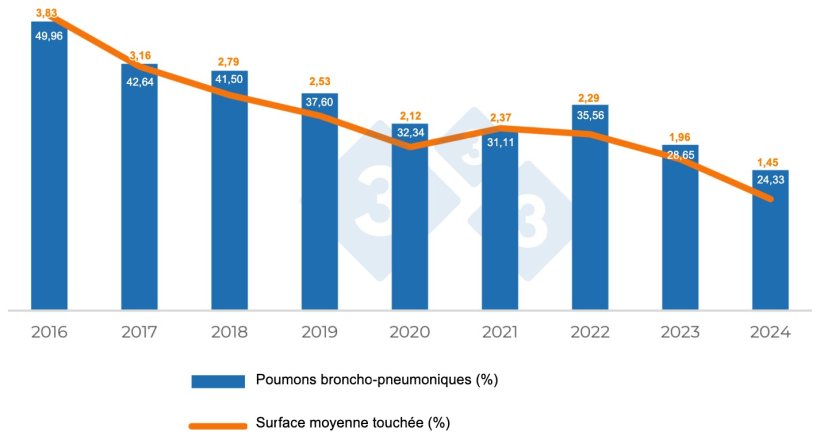

En Espagne, après plus de 6 500 lots et plus d'un million de poumons évalués, nous observons une réduction du degré d'atteinte par des lésions compatibles avec Mycoplasma hyopneumoniae depuis 2016 jusqu'à aujourd'hui (tableau 1 et graphique 1), tant en termes de :

- prévalence des poumons affectés (de 49,96 % à 23,71 %)

- surface pulmonaire moyenne affectée par les lésions (de 3,83 % à 1,39 %)

Tableau 1. Évolution des lésions pulmonaires de 2016 à 2024 en Espagne

| 2016 | 2017 | 2018 | 2019 | 2020 | 2021 | 2022 | 2023 | 2024 |

|---|---|---|---|---|---|---|---|---|

|

Nombre de poumons évalués |

||||||||

| 76.868 | 154.817 | 214.702 | 184.741 | 100.017 | 109.251 | 68.786 | 93.568 | 173.220 |

| % Poumons bronchopneumoniques | ||||||||

| 49,96 | 42,64 | 41,50 | 37,60 | 32,34 | 31,11 | 35,56 | 28,65 | 24,33 |

| % Superficie moyenne touchée | ||||||||

| 3,83 | 3,16 | 2,79 | 2,53 | 2,12 | 2,37 | 2,29 | 1,96 | 1,45 |

Graphique 1. Évolution des lésions compatibles avec Mycoplasma hyopneumoniae.

Nous avons constaté une légère augmentation au cours des années 2021 et 2022, probablement due à des co-infections par des souches hypervirulentes du SDRP qui ont entraîné une augmentation du degré des lésions observées et une détérioration générale de la santé des élevages dans certaines zones.

Cette amélioration observée au fil des ans peut être due à la fois à une amélioration des stratégies de contrôle des problèmes causés par Mycoplasma hyopneumoniae et à l'augmentation observée du poids à l'abattage et, par conséquent, de l'âge des animaux. Ce fait se reflète dans une certaine mesure dans le fait que l'apparition de cicatrices ne diminue pas avec la même intensité que la prévalence des lésions, mais semble plutôt se maintenir, voire augmenter. Il se pourrait donc que bon nombre des lésions aient cicatrisé et ne soient donc pas observées à l'abattoir comme des lésions bronchopulmonaires, mais comme des cicatrices.